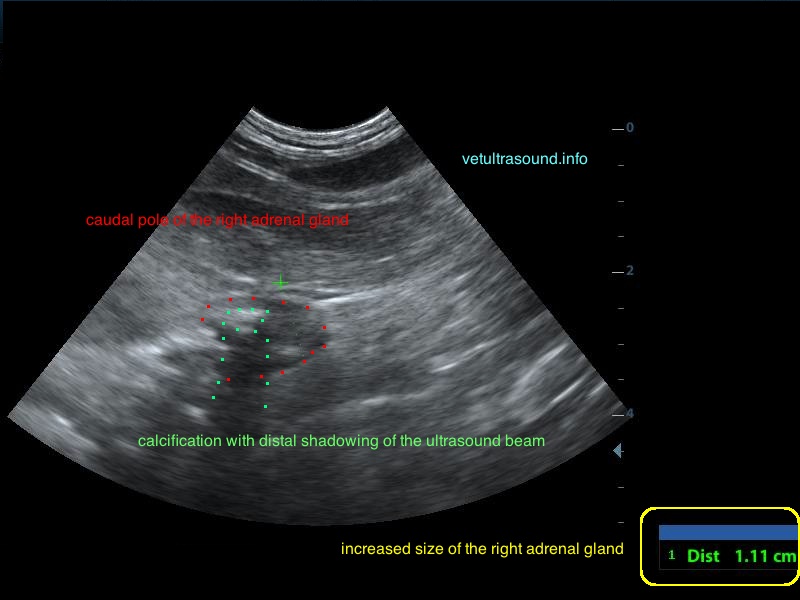

Ήπια ηπατομεγαλία με αύξηση της ηχογένειας του οργάνου, χωρίς παρουσία εστιακών αλλοιώσεων(pic.4). Πάχυνση του τοιχώματος της χοληδόχου κύστης με εικόνα βλεννοκήλης ( kiwi sign) και έντονη υπερηχογένεια στη περιοχή περί αυτού(pic.1&2). Ήπια διάταση της νεφρικής πυέλου, πιθανόν λόγω της πολυουρίας και πολυδιψίας(pic.3). Επασβέστωση στον οπίσθιο πόλο του δεξιού επινεφριδίου και αύξηση των διαστάσεών του(pic.6). Απουσία ασκιτικής συλλογής και παθολογικά διογκωμένων λεμφαδένων.

Η διάγνωση μετά τον υπέρηχο τέθηκε ως βλεννοκήλη της χοληδόχου κύστης με εικόνα χολοκυστίτιδας σε υπόβαθρο πιθανού υπερφλοιοεπινεφριδισμού. Θα πρέπει να γίνει επιβεβαίωση με αιματολογικές εξετάσεις του υπερφλοιοεπινεφριδισμού, καθώς η βλεννοκήλη της χοληδόχου κύστης είναι μία από τις επιπλοκές αυτού.